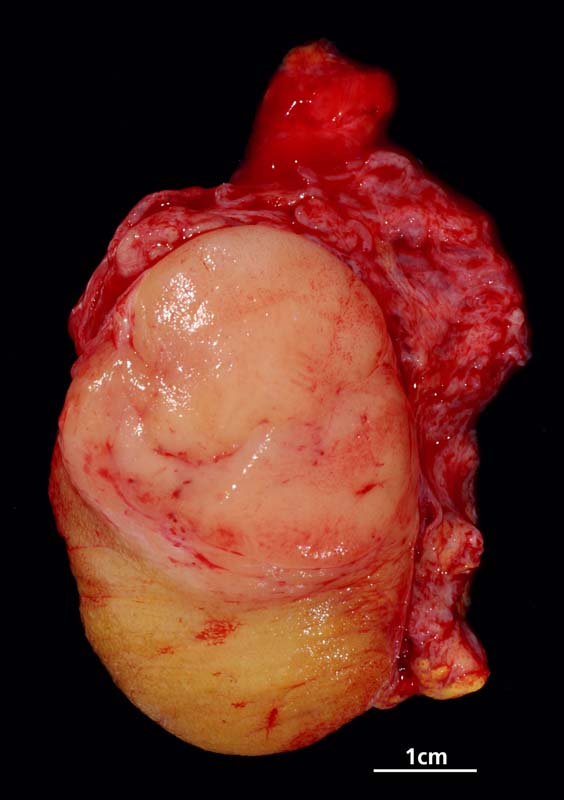

Makroskopisch imponieren Seminome als gut begrenzte weiche crèmefarbene Knoten oder diffuses Intiltrat. Mikroskopisch findet sich eine uniforme Population grosser Zellen mit prominentem zentralem Nukleolus, welche durch schmale Bindegewebssepten voneinander getrennte Nester bilden. Ein leukozytäres Entzündungsinfiltrat, synzytiotrophoblastäre Riesenzellen und Mikroverkalkungen können zusätzlich vorhanden sein. Gelegentlich induziert der Tumor eine ausgeprägte granulomatöse Entzündung. Dies kann zur Fehldiganose einer granulomatösen Orchitis führen.

• Scharf begrenzter Tumorknoten mit eosinophilen Nekrosearealen.